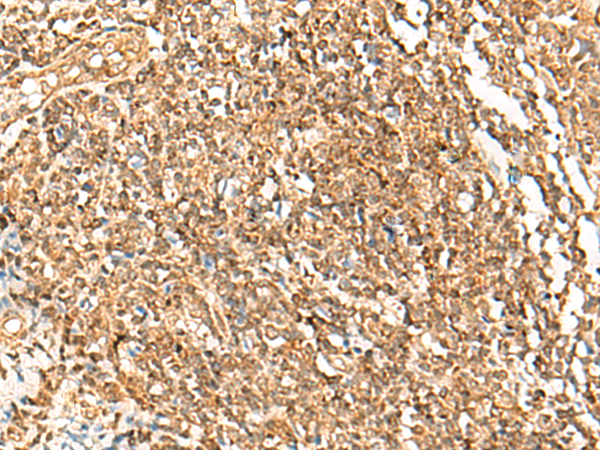

分类: 科研抗体货号: P02876别名: HC9; PSC9; HsT17706应用: WB,IHC反应种属: Human, Mouse, Rat